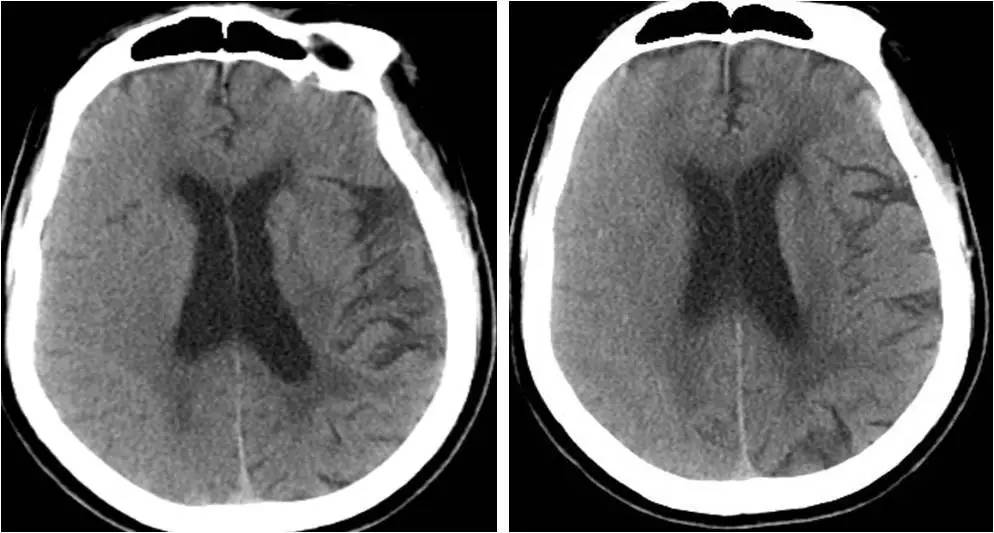

头颅CT:左侧枕叶稍低密度影,左侧基底节区、放射冠、半卵圆中心及丘脑多发腔梗;脑白质变性;脑萎缩。

#头颅CT:传统头部CT通常对于早期识别CHS帮助很小,头部CT提示弥漫性或片状白质水肿、占位效应或术侧颅内出血可能与CHS有关。

#头颅MR:CHS在MRI上的异常表现包括白质水肿、局灶性梗死、局限性或大范围出血等,同时MRA可以对颅内外的血管进行无创评估。但CAS术后目前头颅MR检查相对禁忌。